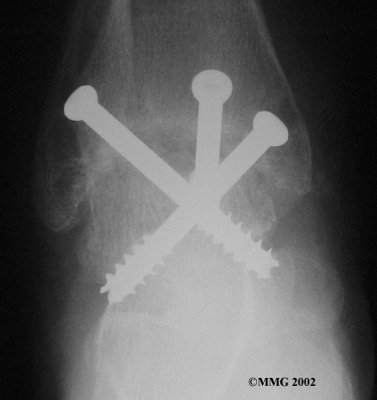

It is important when the surfaces are removed that the angles of the cut surfaces are correct. When the tibia is brought against the talus, the foot should be at a right angle to the lower leg. Once the cuts are made the bones must be held in place while they fuse. This can be done using large metal screws and metal plates if necessary. The screws are usually under the skin and are not removed unless they begin to rub and cause pain.

Inserting the screws

After ankle fusion, the physical therapists at FYZICAL Lakeway can help you learn to walk smoothly and without a limp. Although time needed for recovery varies among patients, an ankle brace will typically replace your cast after eight to 12 weeks. Your surgeon will take X-rays frequently to see if the bones are fusing together. You will probably need to use crutches during the time you wear the cast. As the fusion grows stronger, you will begin to put more weight on your foot when walking.